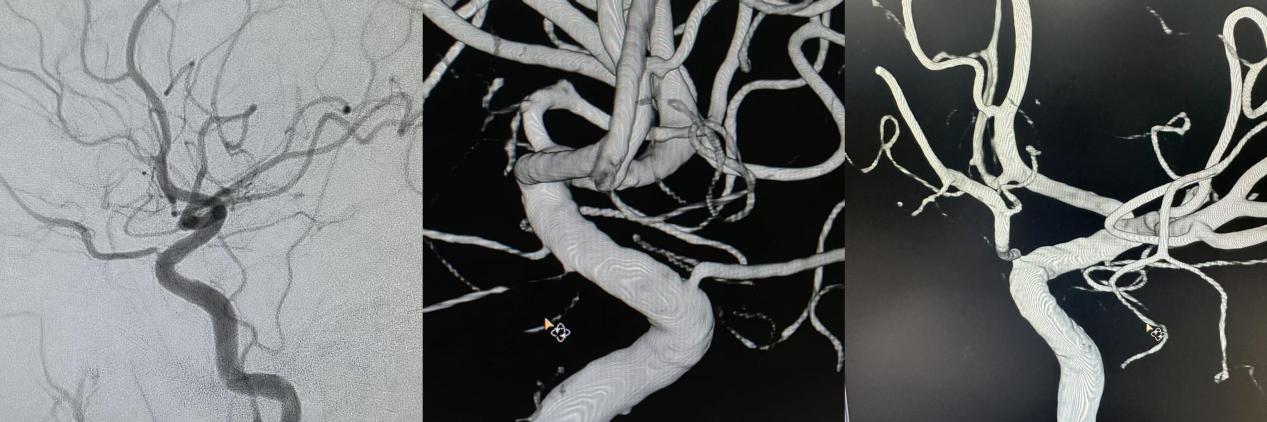

出院1个月后,神经外科团队对患者进行随访,患者语言及左侧肢体障碍已基本恢复。出院后2个月于当地医院复查脑血管造影,显示血泡样动脉瘤已完全闭塞,载瘤动脉通畅。家属对清华大学附属垂杨柳医院神经外科团队的及时救治表示万分感谢。目前患者正在为硕士研究生的新学期做准备。

▲术后3个月复查造影显示动脉瘤闭塞,载瘤动脉通畅